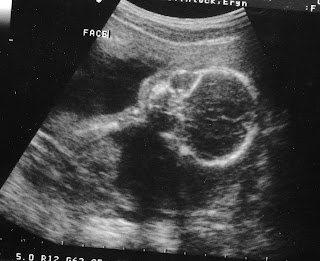

Things are starting to come together for this nursery. A good thing too. This baby is really starting to look like a baby! We had an ultrasound this morning. Baby DB has the most adorable nose and lips you've ever seen in grainy black and white. The critter is still head down and sleeping diagonally in the bed most of the time (just like Dad!). We'll have pictures of the ultrasound as soon as Wesley can get them scanned and some pictures of progress on the nursery sometime after this weekend- when it will be a guest room for Wesley's dad and stepmom who are coming for their first visit to Asheville. Until then... there I am above. You see me? I'm the one hiding behind that huge belly!